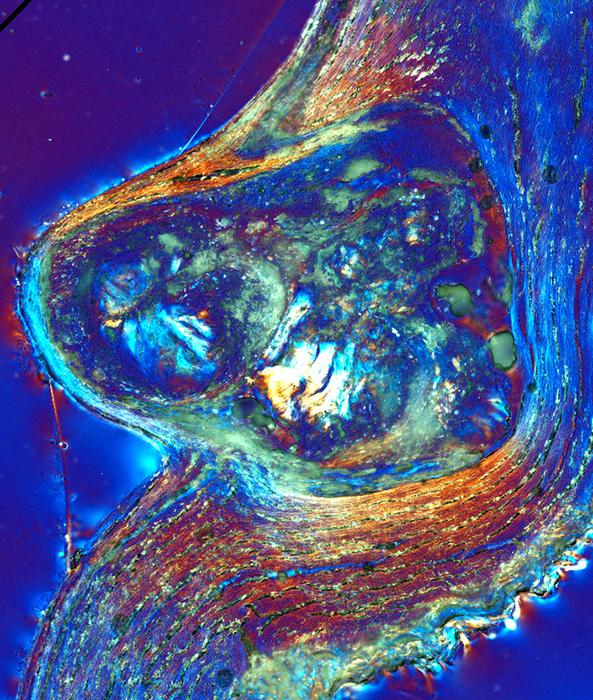

“We used more than 12 modalities of study, including optical microscopy, electron microscopy and spectroscopy, to investigate the nature and progression of mineralization and protein localization in the aortic valve for the first time. This multimodal analysis set us apart, uncovering a new line of evidence to better understand cardiovascular calcification,” Sivaguru said.

The starting point is healthy leaflet tissue. Then tiny spherules of calcium phosphate form in the smooth muscle layer of the leaflets.

As they grow, the spherules coalesce into layers that encrust and stiffen the collagen and smooth muscle fibers that give the leaflets their flexibility. These processes combine to form large nodules that rotate, touch each other and further stiffen the tissues.

The researchers found two defense mechanisms. As the tiny ACP spherules form and begin to coalesce, the heart tissues produce large amounts of the protein osteopontin. Osteopontin promotes apatite growth and calcification in bones and kidney stones, so the findings initially puzzled the researchers, Fouke said. But osteopontin has the opposite, inhibitory effect on ACP, slowing down collagen calcification and nodule aggregation.

The body’s second defense is the very collagen where the nodules form. The researchers found that as the nodules start growing, the collagen fibers stretch around and contain them, forming a water barrier that further slows nodule growth.